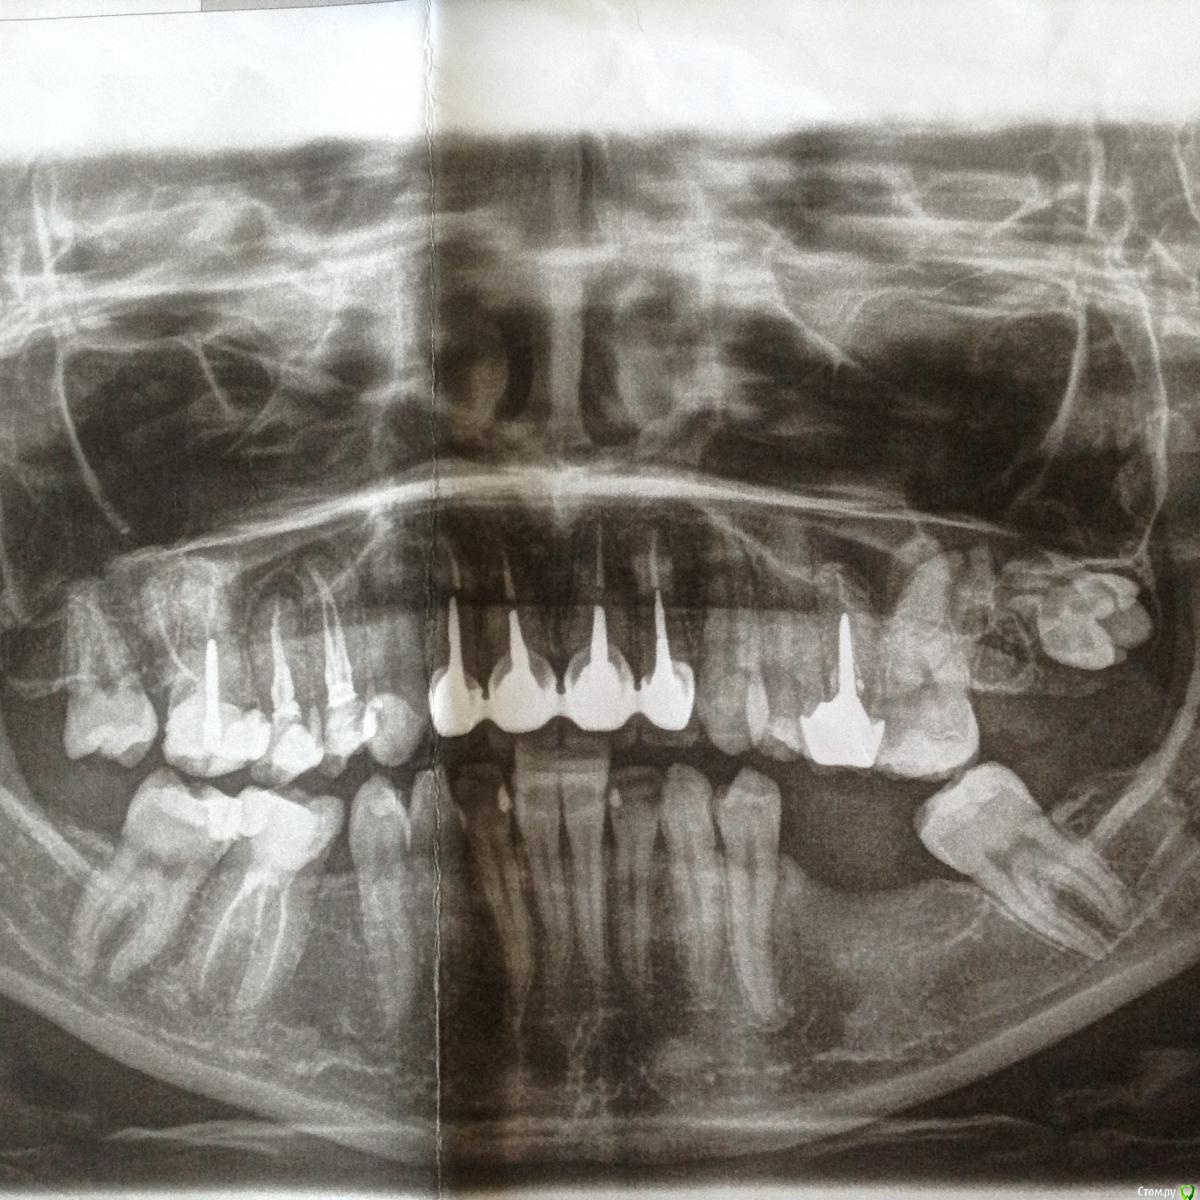

bllack Опубликовано 31 мая, 2016 Автор Поделиться Опубликовано 31 мая, 2016 Вот снимок около года назад Ссылка на комментарий